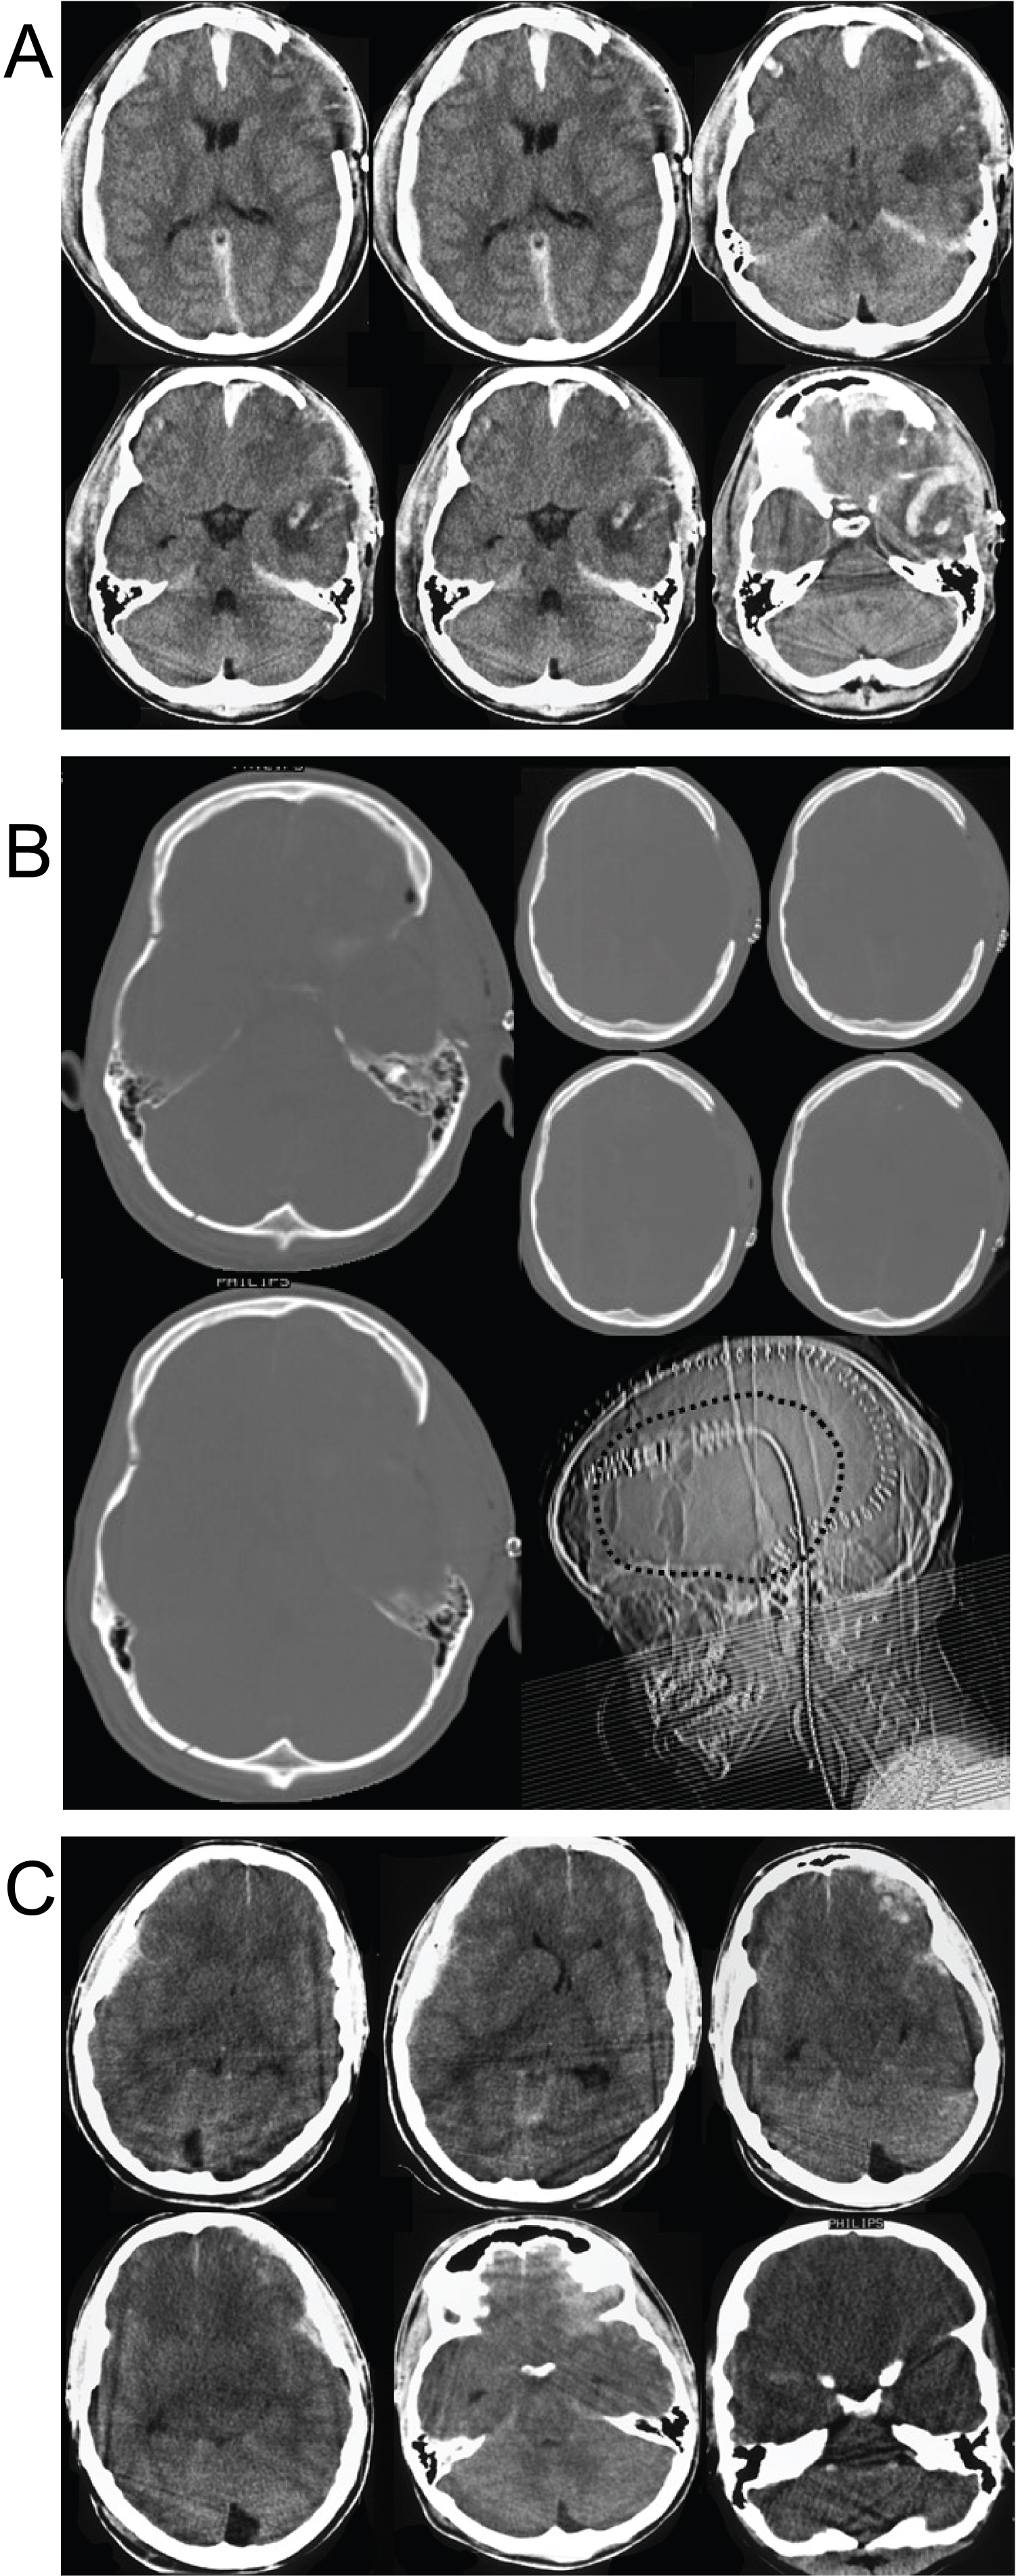

Inclusion criteria were the presence of a severe TBI according to a GCS lower than 8 and diffuse brain injury with generalized oedema without significant mass lesion on initial computerized tomography (CT) scans (Figure 1). Patients with large mass lesions were excluded from the study. The time span between the trauma and the operation was between 30 and 75 min. In accordance with our own management regime, initially, an intraparenchymal pressure transducer was routinely inserted into the frontal region to control ICP. If the initial ICP 30 mmHg or higher (especially with acute bilateral abnormal pupillary widening), immediate unilateral decompressive craniectomy (UDC) was performed (Figure 1).

Figure 2a: (a) Admitting CT scans in a 7 years old child with severe brain injury. Note the diffuse brain swelling, the obliterated mesencephalic cisterns, and the presence of small intra-parenchymal hemorrhages left frontal. The initial ICP after inserting of an intraparenchymal pressure transducer was 36 mmHg (case 15); (2b) Early CT scans of the same child after the UDC showing the sufficient decompression of the mesencephalic region. Note the enlargement of the pre-existing contusions left frontally without a significant mass effect; (2c) Early CT scans of the same child after the UDC showing the bone structure and the craniotomy reaching the temporal skull base and decompress the middle brain area (bone technique). View Figure 2

Both children have at admission initial ICP of 36 mmHg. The admitting CT scans (Figure 2c) in case 15 demonstrated the diffuse brain swelling, the obliterated mesencephalic cisterns, and the presence of small intraparenchymal haemorrhages left frontal. The initial ICP after inserting of an intraparenchymal pressure transducer was 36 mmHg. The postoperative early CT scans of the same child after the UDC showed sufficient decompression of the mesencephalic region, slightly enlargement of the pre- existing contusions left frontally without a significant mass effect (Figure 2a).